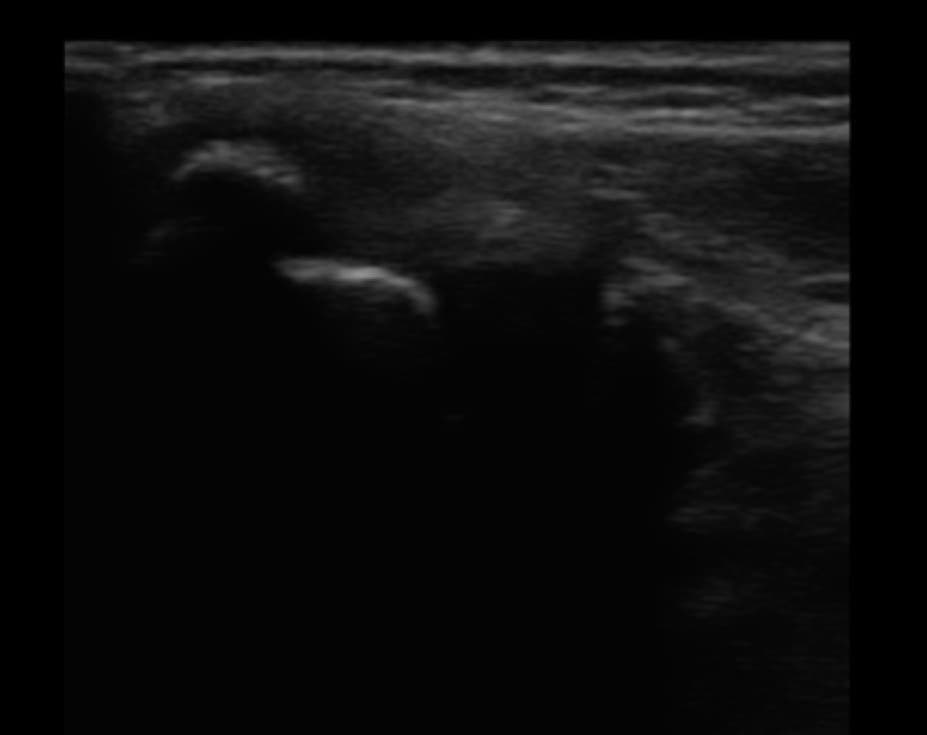

超波エコーによる画像検査

当院では、超音波エコー診断機を取り入れているので骨、靭帯、筋肉、軟骨の状態の把握が出来ます。

どの部分の痛みなのか、どのくらいの治療期間なのか、改善状況もしっかり確認出来るので治療計画が明確にたてられます。

また、重傷の場合や手術が必要な場合などはしっかりと専門機関への受診を勧めますのでご安心ください。